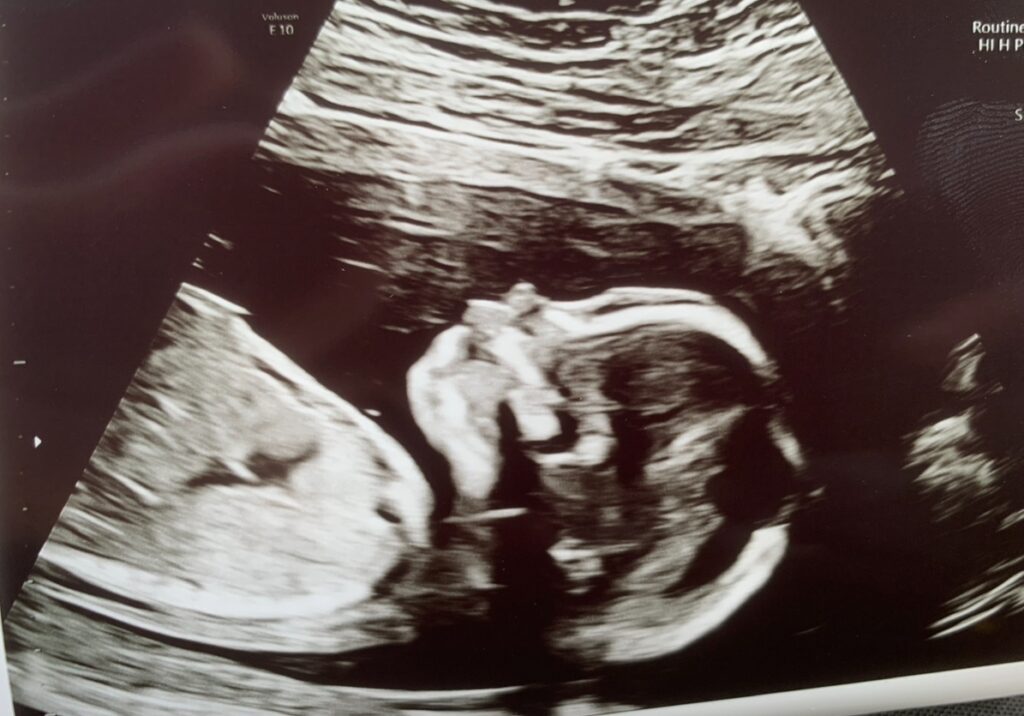

Krigen i Ukraine sætter gravide kvinder i fare, og mødredødeligheden i landet er steget betydeligt.

Fra 2023 til 2024 steg dødeligheden blandt gravide kvinder med cirka 37 procent, viser tal fra en rapport fra 2025, der bygger på tal fra Verdenssundhedsorganisationen (WHO) og organisationen Health Cluster.

– Vores seneste analyse viser en kraftig forværring af mødres sundhed i hele Ukraine, hvor flere kvinder er i fare for at dø, og hvor flere graviditeter ender i livstruende komplikationer, siger Florence Bauer, som er UNFPA’s direktør for Østeuropa i en udtalelse.

Siden Ruslands invasion af Ukraine i 2022 er mere end 80 føde- og neonatalklinikker blevet beskadiget eller ødelagt, oplyser UNFPA.

Ifølge FN-agenturet betyder angrebene mod hospitaler og andre faciliteter, at kvinder bliver tvunget til at føde under “stadig farligere forhold”.

Fra 2023 til 2024 skete der også en stigning af andelen af gravide kvinder, der blev ramt af alvorlige komplikationer. Det gjaldt en stigning på 44 procent i andelen af kvinder, der oplevede livmoderbristninger og 12 procent i andelen med forhøjet blodtryk.